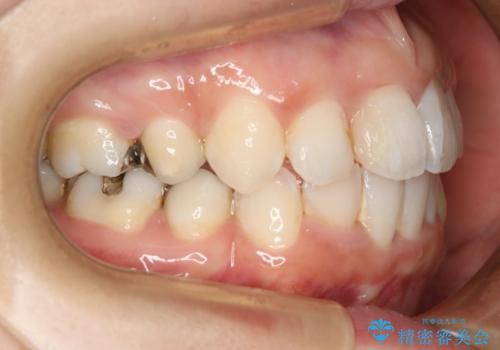

- 歯のガタつきと出っ歯が気になるので矯正治療を希望し来院された患者様です。

上下顎とも歯を並べられるスペースが無く、口元を下げたいというご希望だったので、抜歯とワイヤー矯正を併用した治療を計画しました。

抜歯スペースを利用し口元を大きく下げることが出来ました。